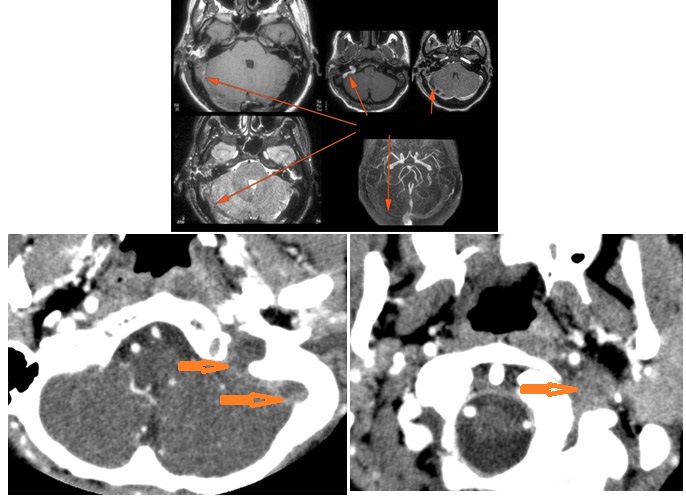

MRI: Anatomically focused axial and coronal images through the temporal bone region and posterior fossa including T1 and T2-weighted acquisitions done with and without gadolinium contrast enhancement and, when indicated, MRV.

There is evidence of thrombosis, thrombophlebitis or other occlusive or inflammatory process of the sigmoid sinus, transverse sinus, the vein of Labbe’ or jugular bulb. [Yes/No]

There is evidence of thrombosis, thrombophlebitis or other occlusive or inflammatory process of jugular vein. [Yes/No]

There is brain edema and/or evolving abscess present or, specifically, involving the inferior temporal lobe or adjacent cerebellum. [Yes/No]

Acute coalescent or otherwise complex otomastoiditis with local complications (indicate specific complications).

Acute coalescent or otherwise complex otomastoiditis with intracranial complications (indicate specific complications).